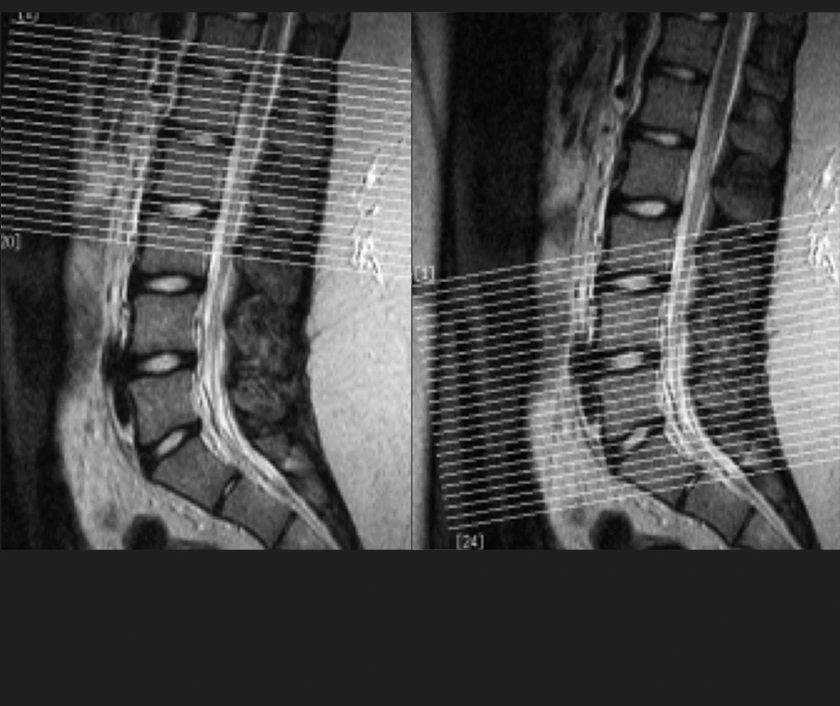

The technical quality of images varies widely from one device to another.

Slide the circle left or right to see how two scanners produce images of the same patient.

In the lower quality image, individual nerve roots and solid organ tissue are difficult to see

Nerve Roots

Organ Tissue

low resolution

high resolution